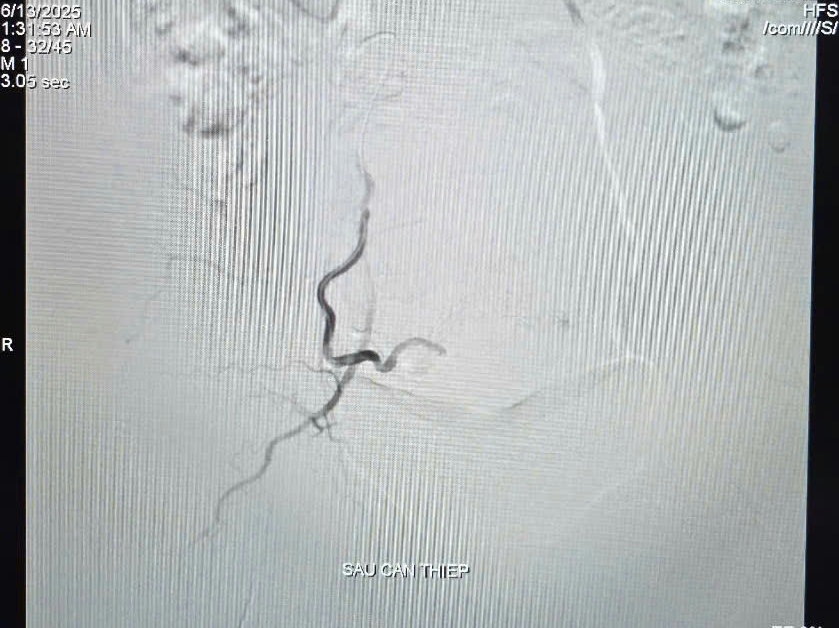

| Hình ảnh tắc động mạch tử cung sau can thiệp. |

Ê-kíp can thiệp do BSCKI Trần Công Khánh, Phó khoa Chẩn đoán hình ảnh đã thực hiện thủ thuật nút mạch tử cung bằng keo sinh học. Hình ảnh chụp cho thấy tử cung được cấp máu chủ yếu từ động mạch chậu trong phải với nhiều nhánh tăng sinh mạch; sau khi xác định vị trí chảy máu, ê-kíp tiến hành tắc mạch thành công sau 45 phút.

Bằng cách làm tắc các nhánh của động mạch tử cung cấp máu đến vị trí chảy máu, việc can thiệp trở nên nhanh gọn, nhẹ nhàng, xấm lấn tối thiểu, dẫn đến sự hồi phục nhanh chóng và ít biến chứng sau can thiệp, đặc biệt là giữ lại được tử cung cho bệnh nhân. Đây cũng là phương pháp được Hội Sản phụ khoa Hoa Kì khuyến cáo như một lựa chọn an toàn và hiệu quả với mức độ chứng cứ cao nhất. Can thiệp nội mạch bên cạnh việc cầm máu điều trị tình trạng xuất huyết, rong kinh, cũng làm giảm các cơn đau rõ rệt.